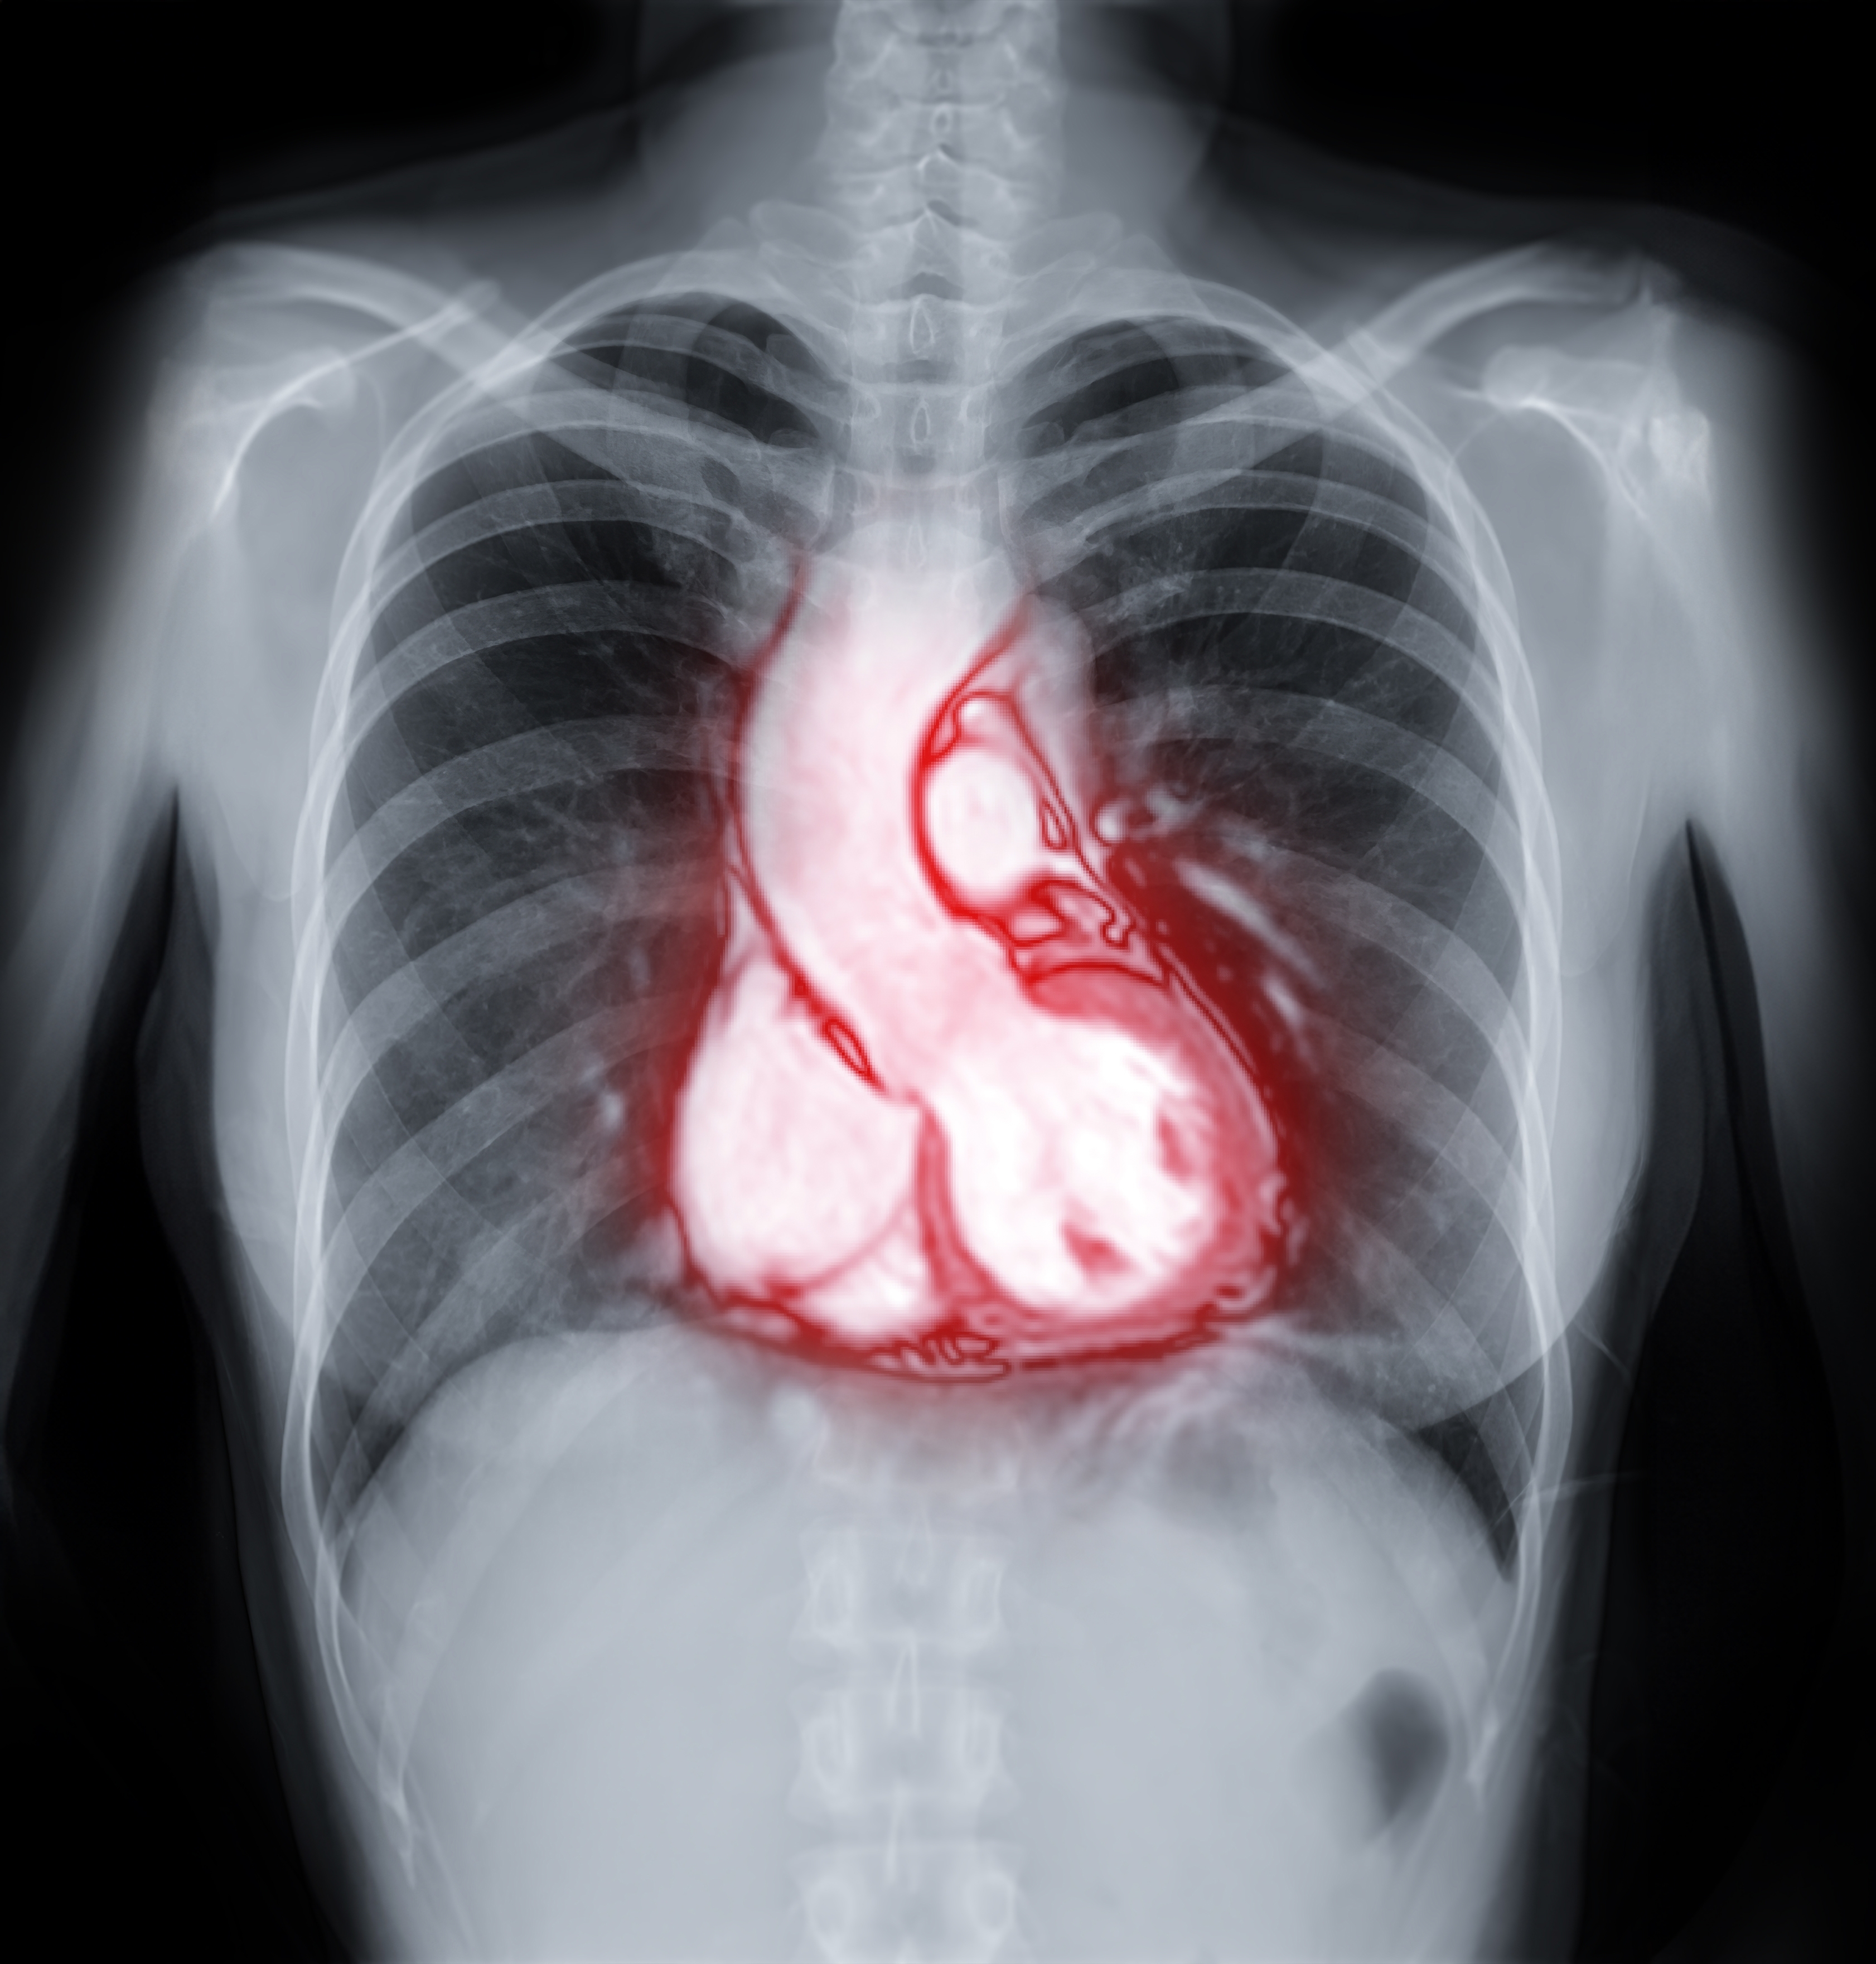

Tras titularse, ya sabía que la academia era un camino que debía preparar. Por eso decidió cursar el magister y doctorado en Ciencias de la Ingeniería en al área de Imágenes Médicas, también en la UC (2007). Su trabajo se centra en emplear técnicas avanzadas de resonancia magnética, un examen no invasivo que es utilizado para detectar alteraciones en tejidos, como el corazón. Estas permiten reducir los tiempos de exámenes, mejorando la experiencia de los pacientes, los costos y la eficiencia del diagnóstico. Siempre pensando en mejorar la accesibilidad en espacios de escasos recursos.

Ya en el país y con iHealth en pleno desarrollo, la investigación de imágenes de resonancia magnética del corazón incluyó de manera más potente las soluciones basadas en la Inteligencia Artificial (IA). Los millones de datos que proporciona esta herramienta permiten, por ejemplo, reconstruir imágenes o corregir el movimiento (problemas inversos) y su aplicación clínica. La IA también ayudaría a predecir de manera automática el desarrollo de una enfermedad en un paciente. Y no sólo eso, también reduciría los tiempos de los exámenes, redundando en menores costos.

Este trabajo de imágenes de alta resolución y múltiples contrastes en tiempo de adquisición reducidos y avances en el mapeo cuantitativo, orientadas a mejorar la caracterización de los tejidos cardiacos y hepático, le significó un reconocimiento internacional en 2024. Fue distinguida por la International Society for Magnetic Resonance in Medicine con el premio ISMRM Fellowship “por sus destacadas contribuciones al desarrollo y avance de los métodos de imágenes cardiovasculares”. Al año siguiente recibió el premio “Innovadoras en Salud”, otorgado por la Cámara de la Innovación Farmacéutica y Mujeres Empresarias de Chile, junto con el anuncio de su titularidad en la UC.

Al ritmo del corazón

Uno de los horizontes de las investigaciones de la académica Claudia Prieto, es lograr disminuir los tiempos de tomas de las imágenes del corazón. Para mejorar este examen, la experta trabaja de una técnica llamada resonancia magnética cardíaca de fingerprinting (huella magnética), que permite cuantificar tres tipos de parámetros de resonancia magnética de forma simultánea, reduciendo las apneas que debe hacer el paciente durante el proceso y los tiempos en que permanece en el resonador.